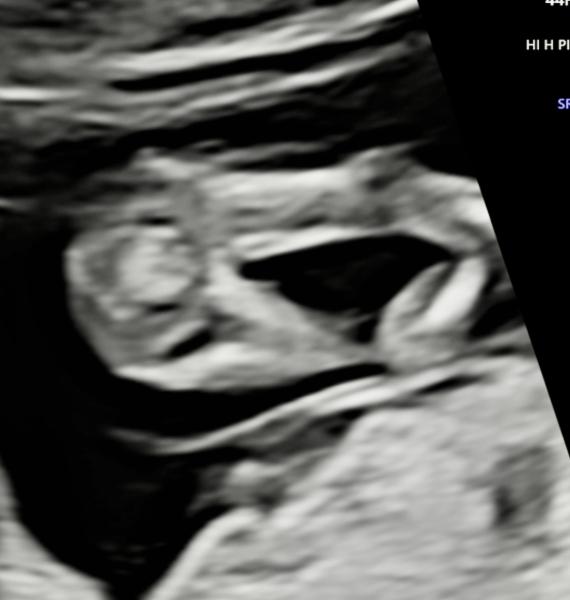

Guten Morgen,  ich bin derzeit in der 13. SSW und hatte letzte Woche einen Ultraschall. Was meint ihr, kann man das Geschlecht erkennen?  Der Arzt hatte eine klare Tendenz die er uns leider bisher nicht mitgeteilt hat.  Ich kann leider nichts wirklich erkennen.  Hier die Bilder aus 12+3. Vielen Dank fürs Miträtseln.